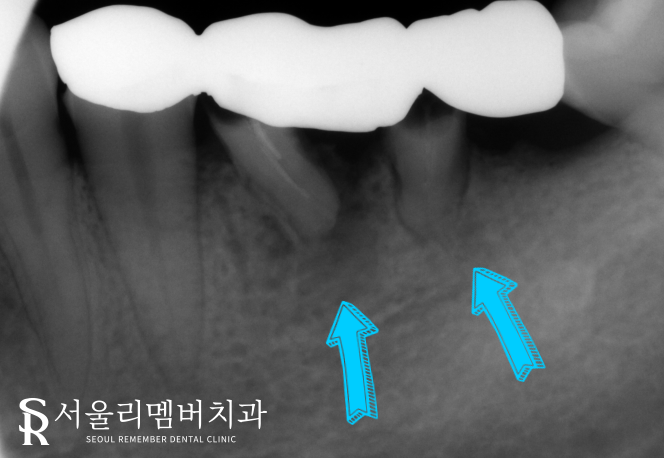

파노라마 사진을 촬영하여 내부까지 확인해 본 결과,

역시나 이곳이 맞았습니다.

브릿지를 올려놨던 곳을 보면 지대치가 부러져

구강 내에 잔존해 있는 것을 볼 수 있는데요.

주변으로 치조골 소실까지 일어난 것으로 보아

염증도 상당히 진행되었음을 확인할 수 있었습니다.